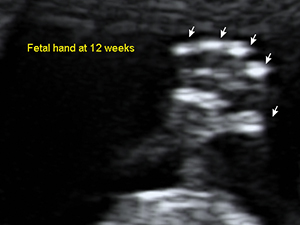

First Trimester